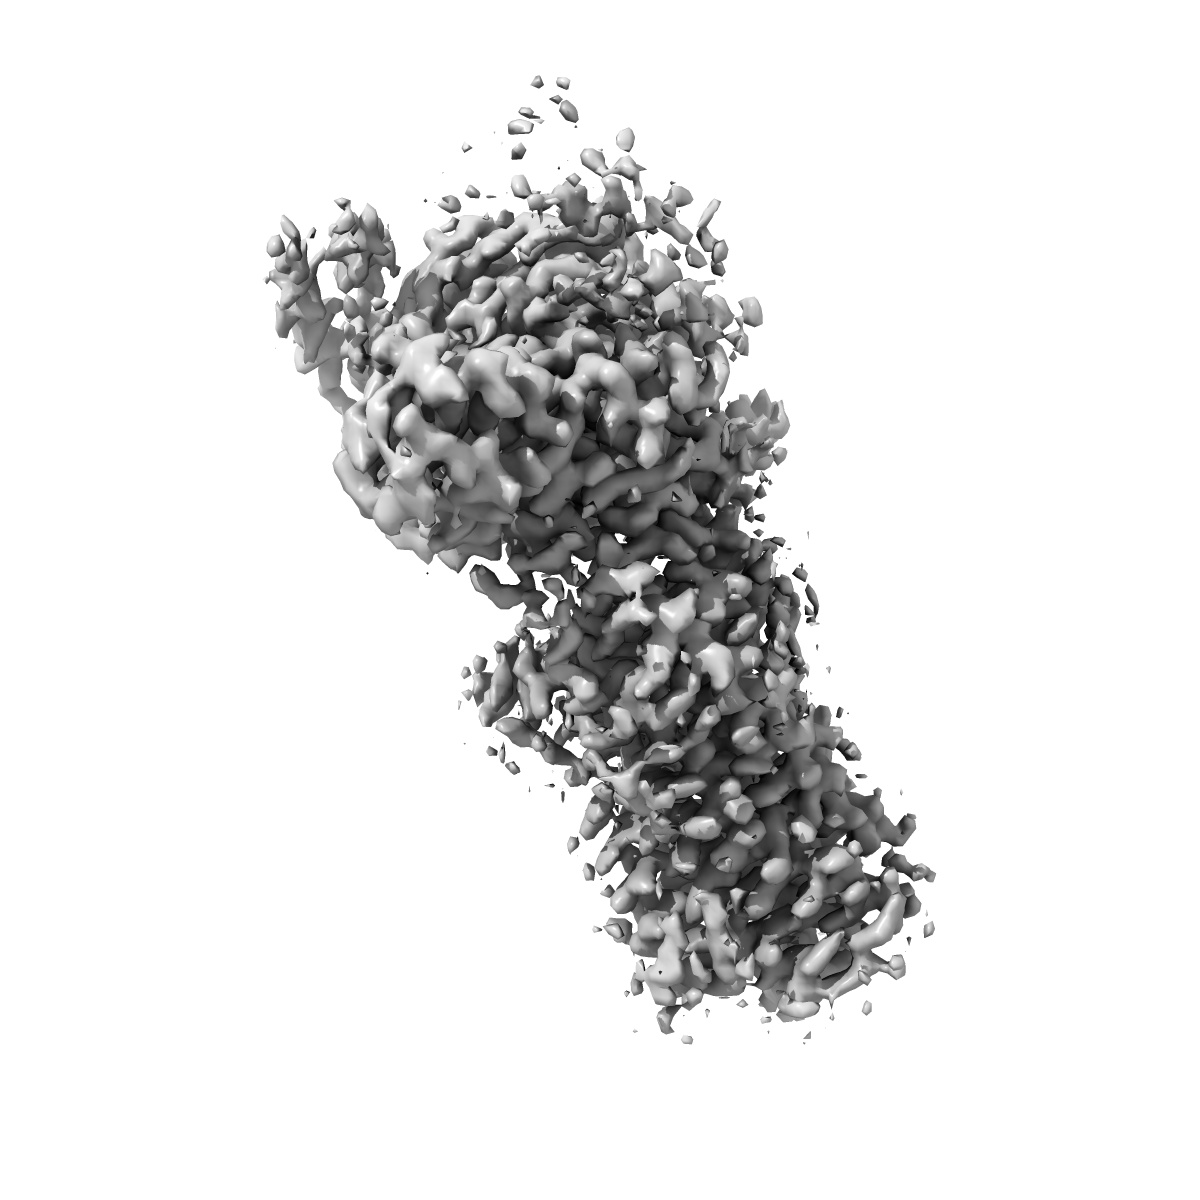

Cryo-EM structure of human angiotensin receptor AT1R in complex Gq proteins and Sar1-AngII

Single-particle2.9 Å

Sample: Angiotensin receptor AT1R in complex with Gq proteins and Sar1-AngII